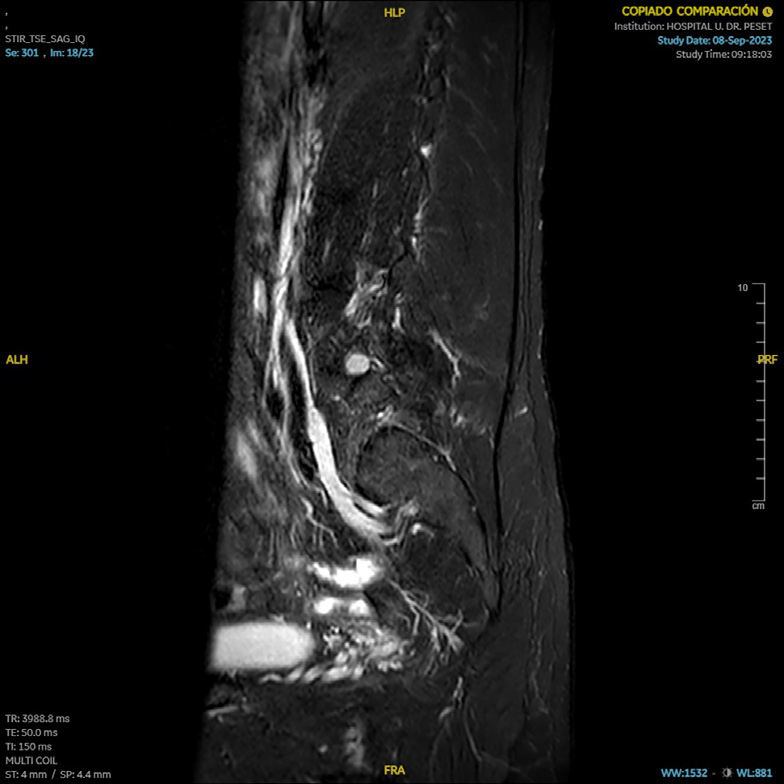

RM (09/2023): cambios postquirúrgicos en L4/L5 con signos de sobrecarga mecánica en platillos vertebrales. Estenosis severa de forámenes neurales L4/L5 por hipertrofia de facetas articulares y por patología discal. Patología en el nivel adyacente L3/L4 con discopatía sin hernia y artropatía degenerativa que producen estenosis moderada foraminal bilateral.

En localización extraforaminal derecha L4/L5, engrosamiento focal sólido de la raíz L4 que mide 15 mm de diámetro y que se realza de forma homogénea tras la administración de contraste intravenoso; sugestivo de tumoración de estirpe neural, neurinoma o neurofibroma.

Schwannoma L4 ho.

La RM de control confirma desaparición de neurinoma.